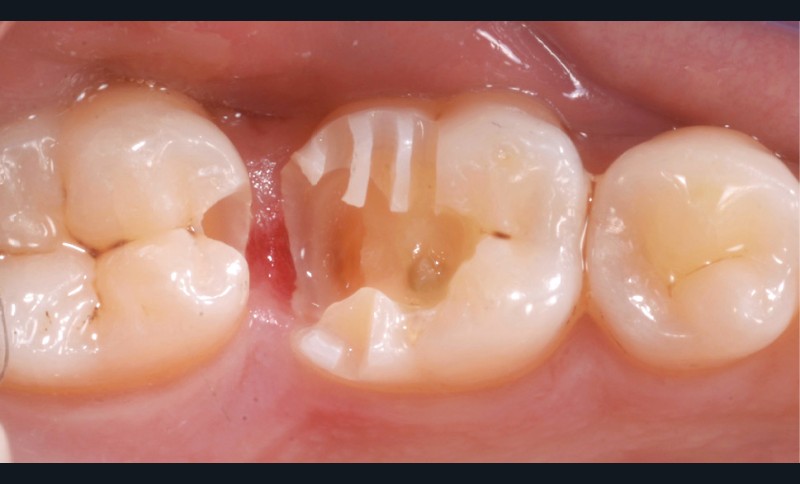

Lors de la préparation d’une cavité pour inlay/onlay, il est fréquent d’être confronté, en fin de nettoyage, à la présence d’une ou plusieurs parois résiduelles dont la résistance mécanique paraît douteuse du fait de leur localisation ou de leur épaisseur. Les parois épaisses (+ de 2 mm) peuvent généralement être conservées (cas clinique 1) et les parois fines (- de 1 mm) doivent généralement être recouvertes. Un inlay (en composite ou en céramique) est alors réalisé. Il doit avoir lui même, au final, une épaisseur globale minimale de 2 mm pour assurer sa résistance mécanique intrinsèque à la mastication. Si un recouvrement cuspidien est indiqué, la réduction occlusale doit donc se faire sur 2 mm de hauteur au minimum [1, 2].

Mais qu’en est-il des parois résiduelles d’épaisseur intermédiaire (entre 1 et 2 mm) (cas clinique 2) ?